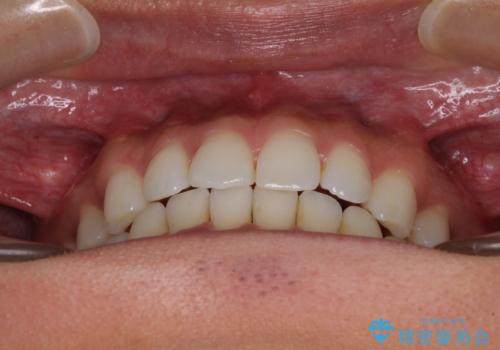

- 上下前歯のデコボコを気にして来院された患者様です。

以前矯正をした後戻りということで、歯列不正はそれほど大きくなかったため、インビザライン・ライトを用いて矯正治療を行うこととしました。

1日22時間以上しっかりと装着してくださったので、半年かからずに治療を終えることができました。